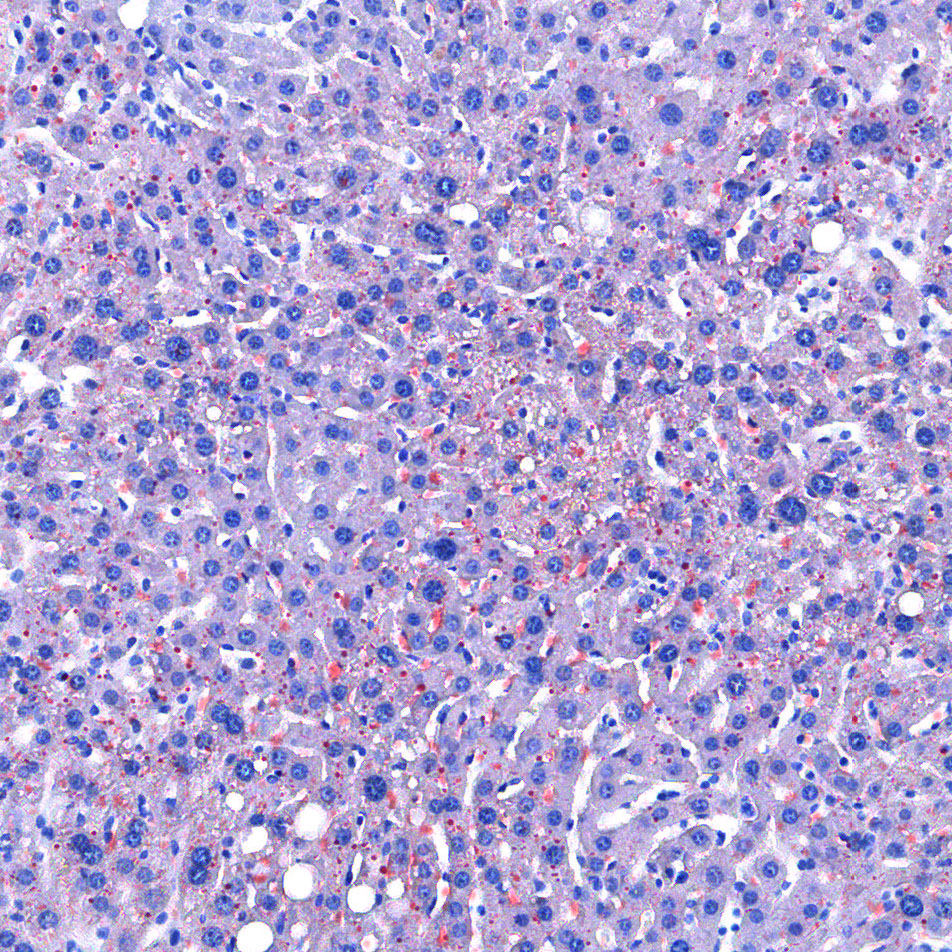

实验结果展示:

<油红O-肝>